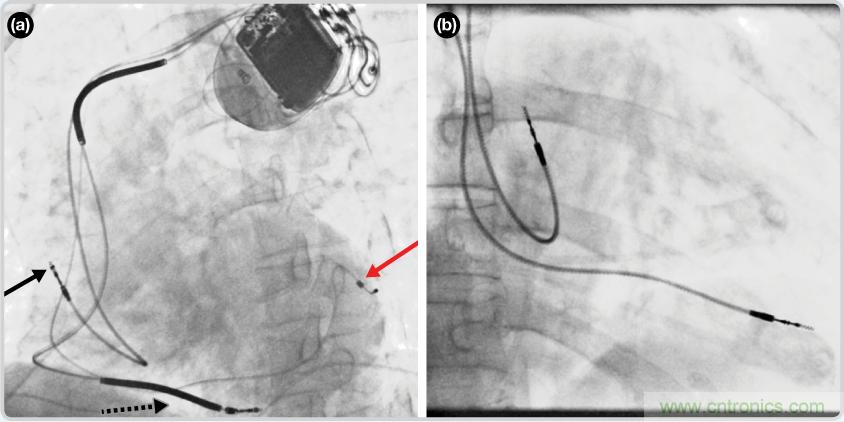

CRT器件在圖4(a)中的透視圖像中可以看見。醫(yī)師就是利用這種影像來放置導(dǎo)聯(lián)線的。對于非專業(yè)人士來說,這種影像是很難解讀的。可以看到心臟淡淡的輪廓——這是搏動中的心臟的靜態(tài)視圖。起搏器位于右心房上,心臟頂點指向右下方。在這個典型的導(dǎo)聯(lián)線放置實例中,黑色箭頭指向右心房導(dǎo)聯(lián)線。虛線黑色箭頭指向右心室導(dǎo)聯(lián)線。紅色箭頭標示的導(dǎo)聯(lián)線只能看到一部分,這是左心室導(dǎo)聯(lián)線(紅箭頭指向電極尖端)。圖4(b)展示的是雙腔起搏器的典型導(dǎo)聯(lián)線放置透視圖像。右心房導(dǎo)聯(lián)線指向上方,置于右心房中。右心室導(dǎo)聯(lián)線則位于右心室頂部。

檢測并區(qū)分心臟起搏偽像

圖4. 起搏器導(dǎo)聯(lián)線放置的透視圖像3 (a). 單腔起搏器;(b).雙腔起搏器